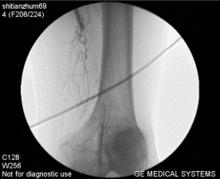

3、動脈造影和數字減影血管造影:是最精確的檢查方法,也是目前診斷血管疾病的重要手段之一。它對於診斷動脈閉塞性疾病有著重要的價值。動脈造影不僅能清楚顯示動脈的形態,明確動脈阻塞的部位,也能詳細地了解阻塞部位遠端血管以及側支循環建立的情況,有助於確定外科治療方案及估計手術預後。然而,這畢竟是一種介入性檢查方法,尤其是造影劑可能對腎功能不全的患者套用受限。因此,該方法多用於需要手術或經皮介入治療的病人。目前動脈造影技術主要套用於血管外科手術前後,除套用於診斷血管疾病外,還可以藉助造影法進行狹窄血管的擴張、血管栓塞、血管內支架等血管介入性治療等。

6、血管造影:血管造影一直被作為ASO診斷的“金標準”,經腰部腹主動脈穿刺或經股動脈穿刺插管造影術可以提示動脈病灶的確切範圍、是否為多發性以及動脈阻塞程度,也可了解側支循環建立的情況,是制定手術方案所不可缺少的檢查方法。